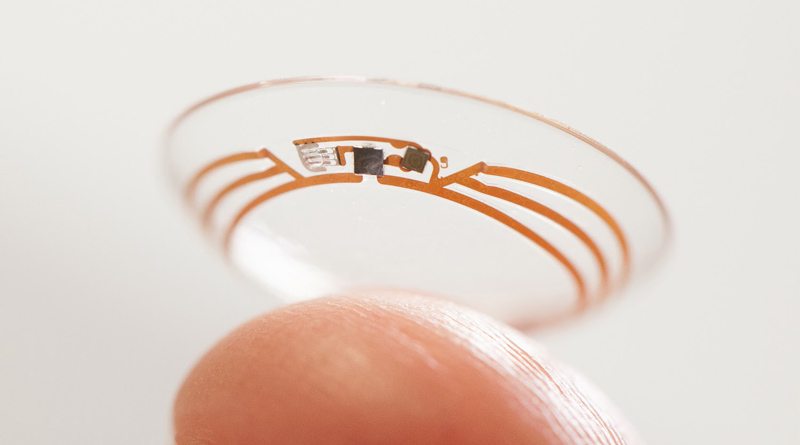

О том, что Google и Novartis начали совместную работу над умными линзами стало известно в 2014 году. В настоящее время разрабатывается два типа линз. Первые предназначены для людей, страдающих диабетом. Разработчики хотят встроить в структуру линзы специальный датчик для измерения уровня глюкозы. Полученную информацию можно будет передавать на смартфон, что позволит более эффективно и своевременно отслеживать данные.

Второе направление — разработка самофокусирующихся линз, которые должны помочь при восстановлении зрения.